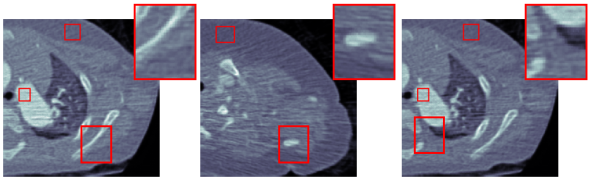

We choose three representative low-dose CT images in the test dataset as shown in Fig. 3(a) for qualitative evaluation. The corresponding denoised images by CCADN, MCCAN without local cycles, MCCAN without global cycles, and MCCAN are shown in Fig. 3(b)- 3(e) respectively. Numbered areas are homogeneous regions, while areas with edges between heterogeneous regions are zoomed for visibility in Fig. 3. From the figures we can see that CCADN can successfully reduce noise in the original images. MCCAN without local cycles completely fails to produce reasonable results. A more closer examination of the images reveal that interestingly the background and the substances are approximately swapped compared with the original images. This is because the high-level features of content distribution are still kept even with such swap, and the discriminator cannot identify the generated image as “fake” because of the structure diversity in the training dataset. This aligns with our discussion on the importance of local cycles in Section 2. On the other hand, MCCAN without global cycles can successfully denoise the image and achieves similar quality compared with CCADN. This is expected as MCCAN without global cycles is essentially formed by two cascaded CCADNs. Finally, with both local and global cycles, the complete MCCAN has the smallest noise visually.

Five homogeneous areas chosen by radiologist are used for the quantitative evaluation, which are annotated by red rectangles in Fig. 3 and numbered from 1 to 5. The normalized quantitative results are shown in Table 1. CCADN can reduce the standard deviation in the five areas by 15%, 21%, 21%, 22% , and 22% respectively, with resulting mean values close to those of the original images. Although MCCAN without local cycles achieves smallest standard deviation in Areas 1, 3 and 4, it leads to meaningless output with large mean deviation from the original images, which corresponds to the structure loss in Fig. 3(c). MCCAN without global cycles has similar performance compared with CCADN. with mean values close to original and standard deviation reduction by 22%, 23%, 20%, 27%, and 19% respectively. Finally, the complete MCCAN behaves the best among all the methods: Within reasonable mean range, the standard deviations are decreased the most by 24%, 32%, 29%, 29%, and 32% from the original CT images respectively.